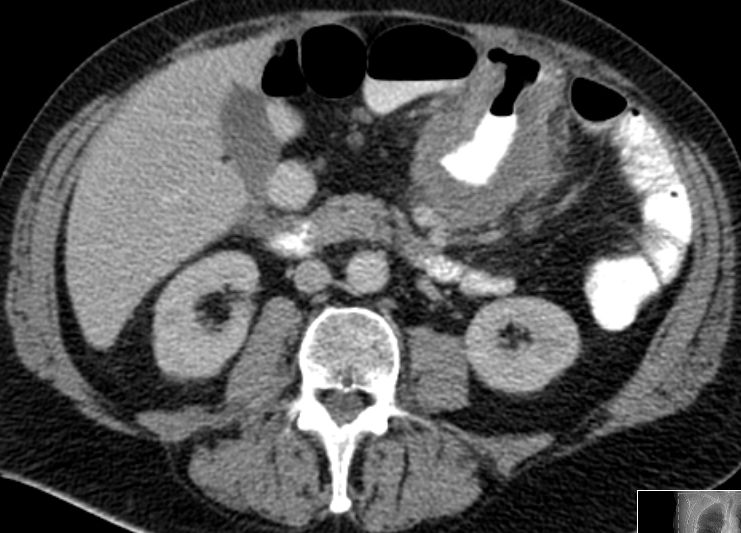

Stenosierender Tumor der linken Flexur mit Ileus.